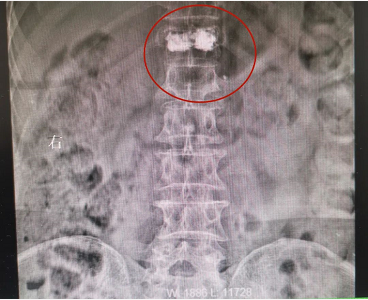

患者骨水泥椎体成形术术后影像

患者郭某,女,64岁,不慎摔倒,腰背部疼痛伴活动受限2天,休息后症状不见好转,就诊于我院脊柱科。X线片提示胸T12椎体压缩性骨折。完善术前相关检查后,来院第二天予患者行胸T12骨水泥椎体成形术,手术约30分钟后,患者自觉腰背部疼痛明显减轻。术后第二天拍片复查后,患者带腰围可下床自行活动。